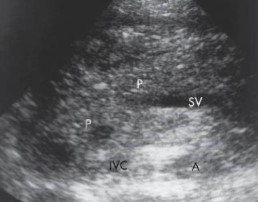

List the 4 landmarks that lie behind the pancreas.

Aorta/IVC

Superior mesenteric vein and Superior mesenteric artery

Splenic vein

Portal confluence

What is the typical AP measurement for the pancreas?

Less than 3 cm

What measurements are these?

What is the normal measurement for these?

AP

Less than 3 cm